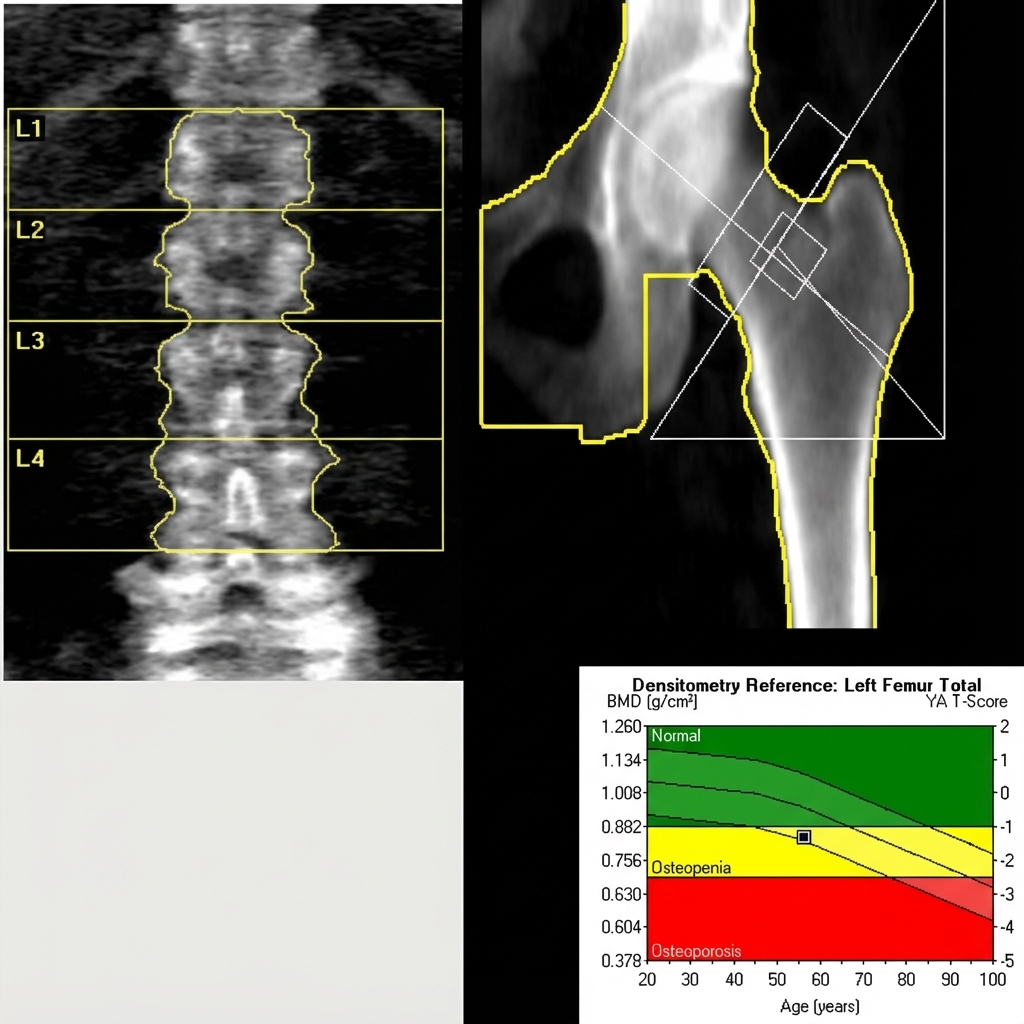

골밀도 검사(BMD)는 뼈의 밀도(단단한 정도)를 측정하여 뼈의 건강 상태를 평가하는 검사입니다. 우리 병원에서는 주로 이중 에너지 X선 흡수 계측법(DEXA)을 사용하여 요추(허리뼈)와 대퇴골(고관절)의 골밀도를 정밀하게 측정합니다.골다공증은 특별한 증상 없이 진행되다가 작은 충격에도 뼈가 부러지는 심각한 골절로 이어질 수 있습니다. 골밀도 검사는 이러한 골다공증을 조기에 발견하고, 골절 위험도를 예측하여 적절한 예방과 치료를 시작하는 데 필수적입니다.

검사 결과는 주로 ‘T-점수(T-score)’를 통해 젊은 성인의 평균 골밀도와 비교하여 판단합니다.

정상 (Normal): T-점수 -1.0 이상

뼈가 건강한 상태입니다. 현재의 생활 습관을 유지하며 정기적인 검진을 권장합니다.

골감소증 (Osteopenia): T-점수 -1.0 미만 ~ -2.5 초과

골다공증으로 진행될 위험이 있는 단계입니다. 칼슘/비타민D 섭취와 운동 등 관리가 필요합니다.

골다공증 (Osteoporosis): T-점수 -2.5 이하

뼈가 매우 약해져 있어 골절 위험이 높습니다. 약물 치료와 적극적인 생활 습관 교정이 필수적입니다.